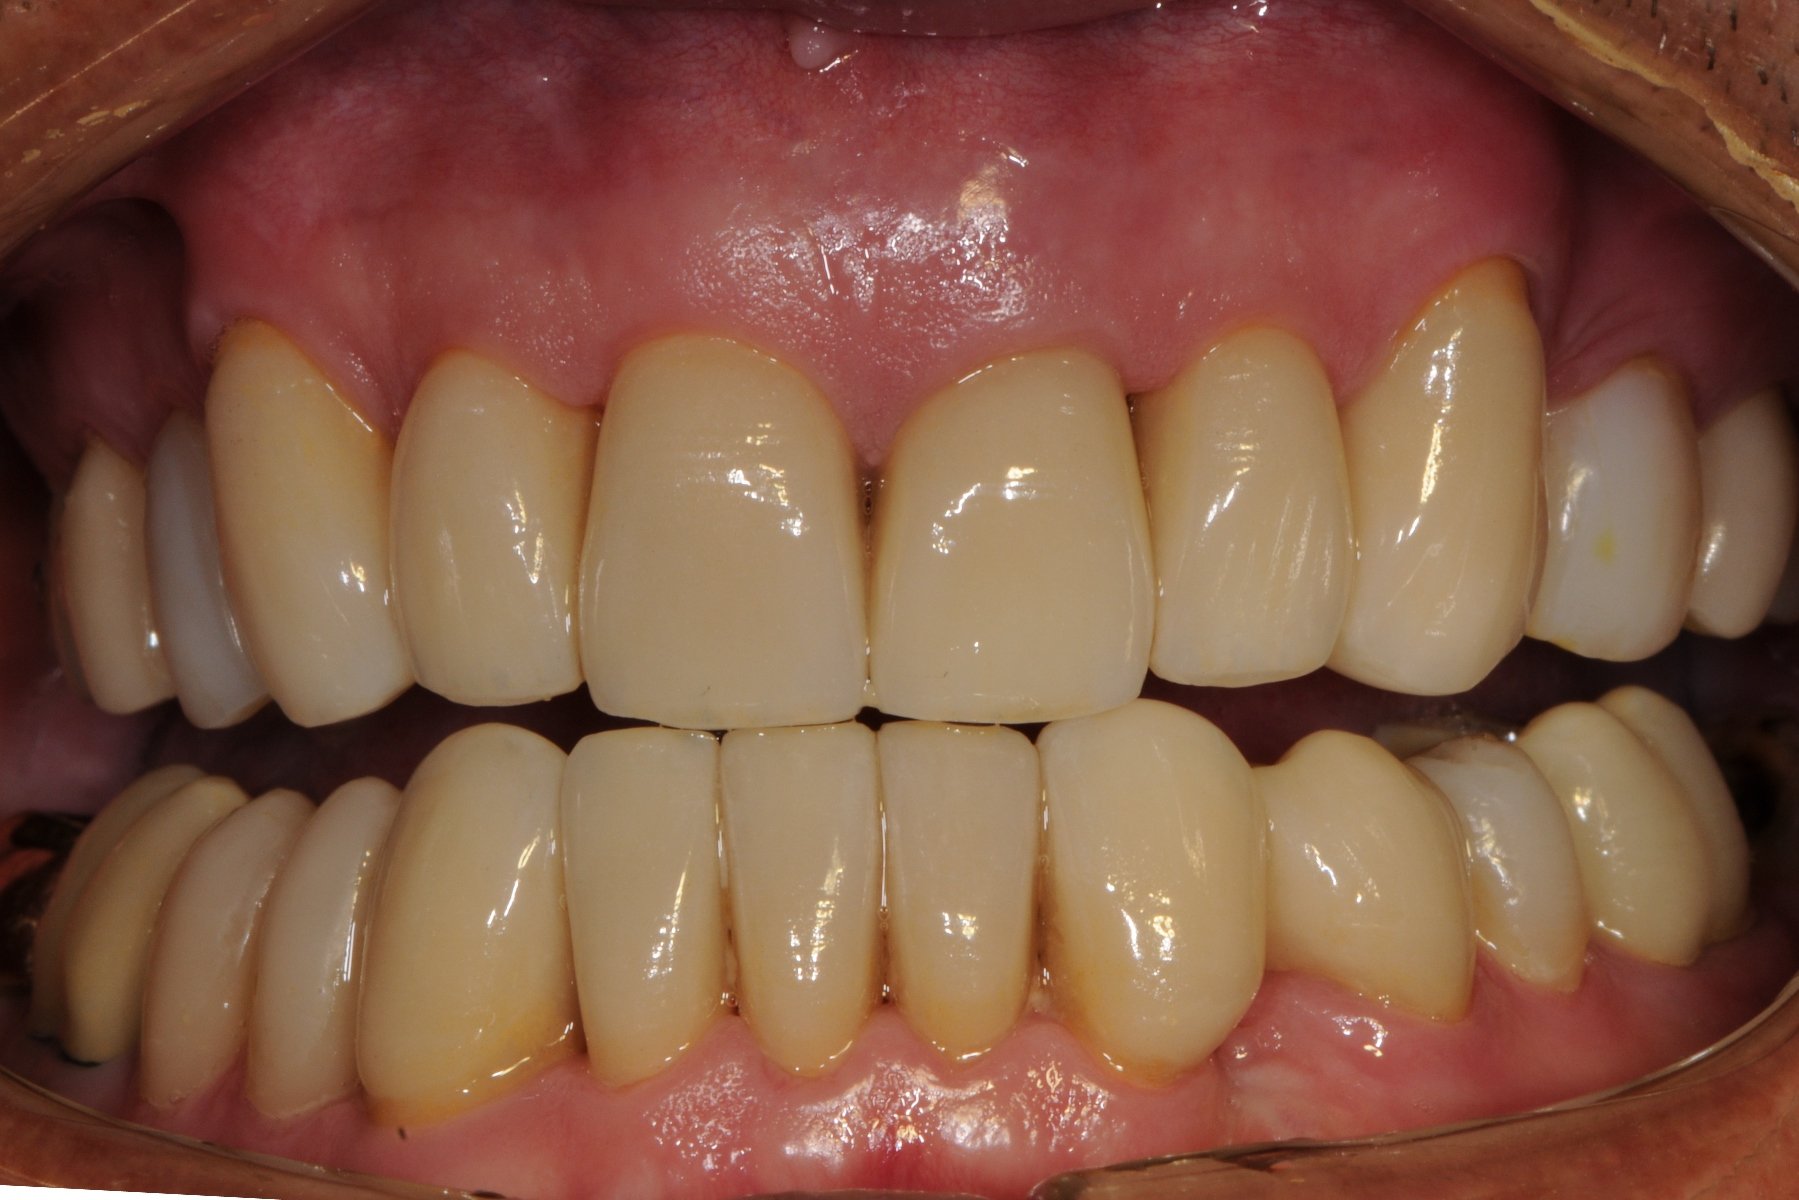

The removeable implant denture in place with a normal overbite and the decay removed and fillings placed.

The red carbon paper biting marks on the teeth illustrate a protective balanced hinge bite which is responsible for keeping the lower implant denture stable when chewing.

The final photograph of the implant denture supporting the lower lip and an improvement to the aesthetics of the upper teeth. The patient is currently treatment planned to completely replace the stained top left number 2 lateral incisor with a white bridge and other front teeth with aesthetic Zirconia/Porcelain crowns to colour match the whiter implant denture. The patient has returned twice yearly for a Continuous Care Appointment CCA for examination, fine tune bite adjustment and airbrush cleaning with chalk, air and water around the implant gumline followed by a fluoride application. The telescopic implant denture is now on its 10th year of longevity.